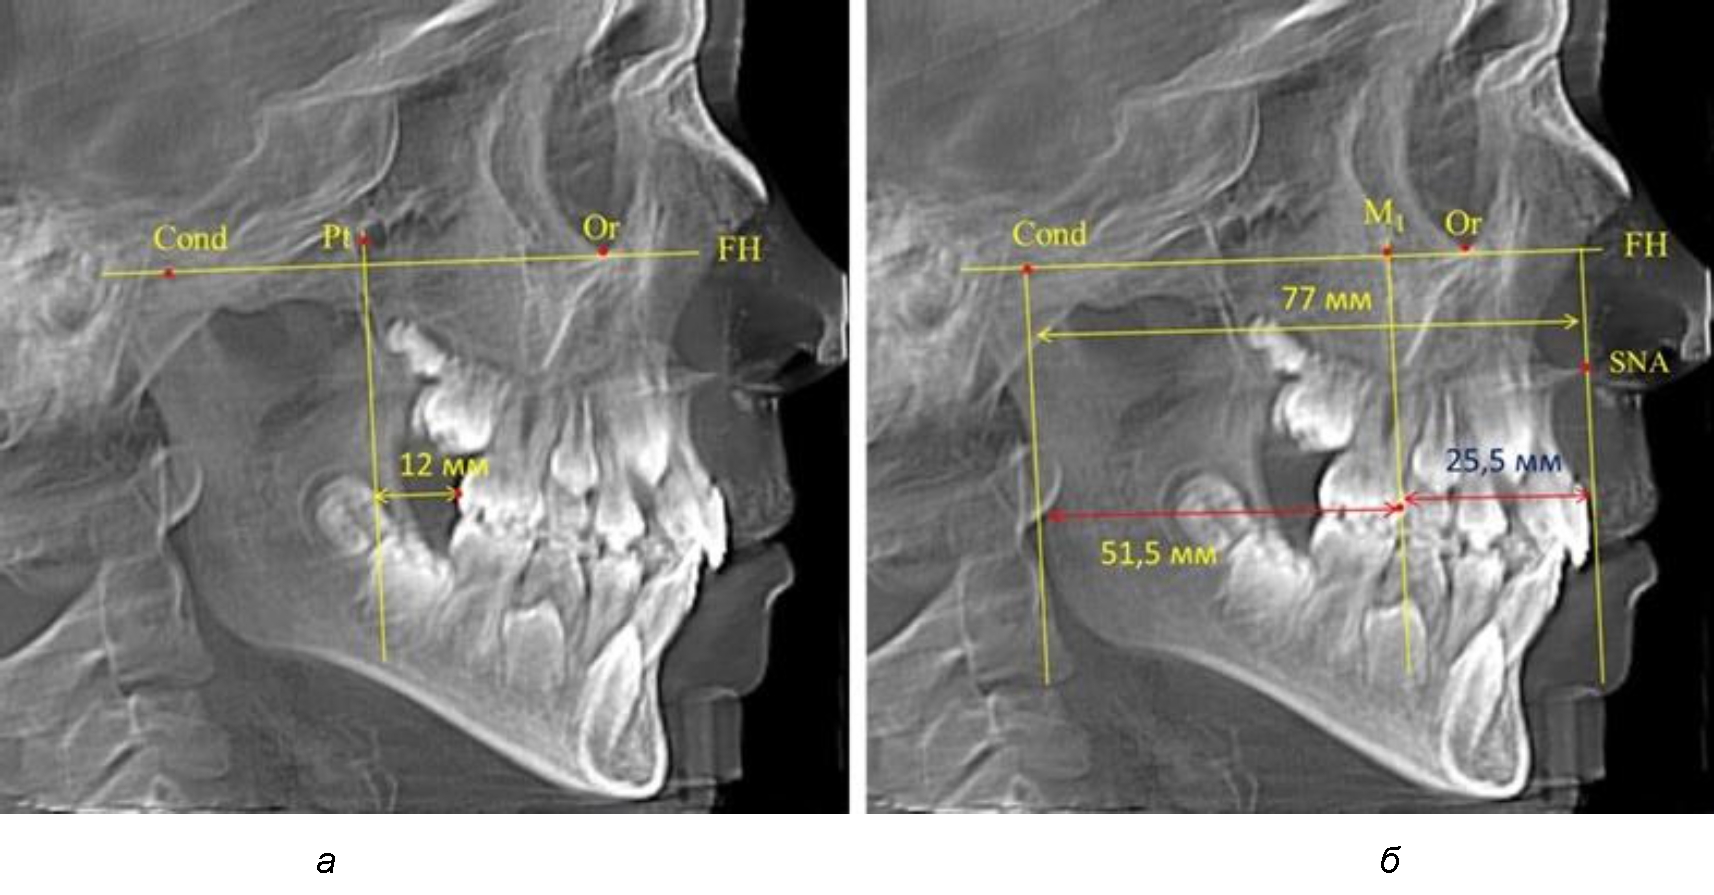

Рис. 2. Особенности положения первых моляров по R. E. McDonald (а) и по предложенному методу (б) при уменьшенном молярно-крыловидном расстоянии

Так, при расстоянии от крыловидной вертикальной плоскости PTV до дистальной поверхности верхнего первого постоянного моляра в 13 мм сагиттальный размер гнатического отдела был 82 мм. При этом отношение кондилярно-спинального расстояния к кондилярно-молярному размеру (54,5) было близким к коэффициенту 1,5, что представлено на рис. 2.

Рис. 3. Особенности положения первых моляров по R. E. McDonald (а) и по предложенному методу (б) при увеличенном молярно-крыловидном расстоянии

В то же время при увеличенном расстоянии от крыловидной вертикальной плоскости PTV до дистальной поверхности верхнего первого постоянного моляра, равное 23 мм, сагиттальный размер гнатического отдела составил 92 мм. При этом отношение кондилярно-спинального расстояния к кондилярно-молярному размеру (30,5), так же, как и при малых размерах, было близким к коэффициенту 1,5, что представлено на рис. 3.